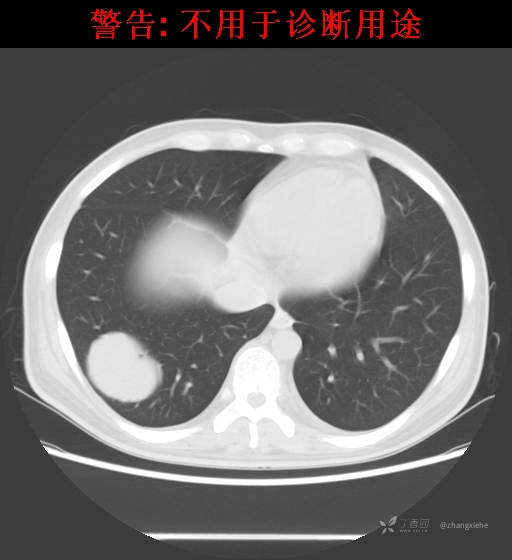

现病史:患者2022-02-07在市中医院体检发现右肺占位,胸部CT示:右肺下叶基底段见一不规则软组织密度影,增强扫描呈轻中度强化,可见血管贴边征。当时无任何不适。2022-02-24于省肿瘤医院行纤支镜检查阴性,痰检未找到癌细胞。经皮肺穿刺细胞学检查找到高度癌疑细胞,病理示:右下肺穿刺考虑神经内分泌癌。免疫组化结果:CgA(-)、CD56(-)、Syn(+)、CK广谱(-)、p40(-)、P63(少量+)、TTF-1(-)、Ki-67(+,40%)、NapsinA(-)、Calcitonin(-)、TG(-)。ECT示:全身骨扫描未见明确骨转移征象。患者出现贫血且逐渐加重、低蛋白血症,予人促红素注射液、精蛋白重组人胰岛素混合注射液、人血白蛋白对症处理,效果不明显,病情加重,右髋出现疼痛,不能行走。2022-03-04转院南大二附院进一步治疗,2022-03-20行右侧髂骨穿刺活检术,术后病理结果示:考虑软组织透明细胞肉瘤。免疫组化示:瘤细胞Vim(+)、NSE(+)、S-100(+)、SOX10弱(+)、Melan-A(+)、TFE-3部分弱(+)、CK(-)、MyoD1(-)、Desmin(-)、HMB45(-)、CD34(-)、CD68(-)、CR(-)、Ki-67约15%(+)。特殊染色示:网状纤维染色(-)、PAS(±)。

2022-03-05血常规示:血红蛋白:64g/L,生化示:白蛋白20g/L。骨髓涂片细胞学检查示:骨髓增生明显活跃,粒红比减低。粒、红、巨三系增生明显活跃。粒系伴成熟障碍。髓片浆细胞较易见,占7%。粒系增生明显活跃,核明显左移,可见巨幼样变及核浆发育不平衡。PET-CT示:1.右肺下叶软组织肿块、右侧耻骨下支及耻骨联合处骨质破坏伴软组织肿块形成,FDG代谢均异常增改,考虑恶性病变,建议病理检查;右侧髂血管旁、双侧腹股沟淋巴结反应性增生,建议随访。2.多浆膜腔(双侧胸腔、心包腔、盆腔)少量积液。3.全身骨骼FDG代谢弥漫增高,考虑骨髓反应性增生。4.大小肠条片状FDG代谢增高,考虑生理性摄取。5.右侧上颌窦面膜下囊肿,脑部FDG代谢未见明显异常。6.C7-T1层面后纵韧带钙化。患者乏力加重,卧床不起,不能承重,大小便不顺畅,转院至我院。门诊拟“1.右肺占位并右侧骨盆转移2.低蛋白血症3.中度贫血 4,血糖升高(原因待查)”收入住院。患者发病以来,无胸闷、胸痛,无呼吸困难,偶咳嗽,无咳血,饮食、睡眠欠佳,2个月之内体重减轻约10kg。